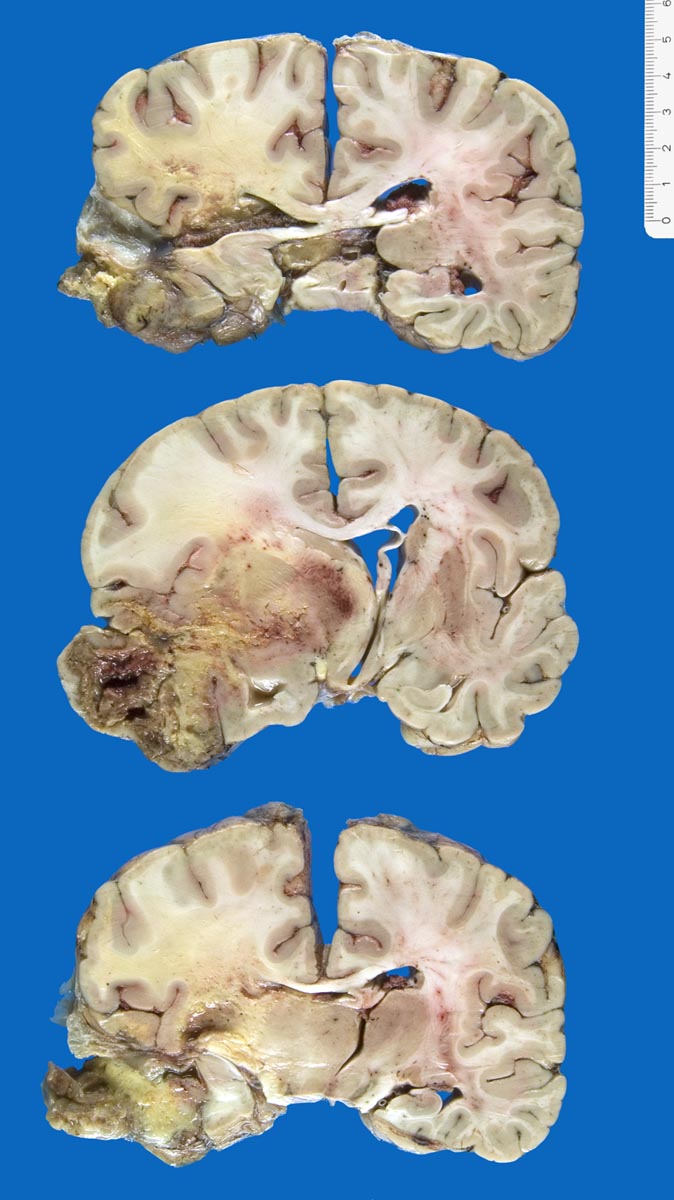

Glioblastoma multiforme

Tumor (Durchmesser 9x8x7cm) links temporal mit zentraler Nekrose und Einblutugen. Mittellinienverschiebung um 1cm und subfalxiale Herniation nach rechts. Einbruch des Tumors in das Ventrikelsystem des Hirns. Einblutung in die Stammganglien.

Histologisch Rest-/Rezidivtumor eines Glioblastoma multiforme (WHO Grad IV) mit ausgeprägten aktinischen Veränderungen.

Glioblastoma multiforme parietal links. WHO Grad IV, Erstdiagnose vor 2 Jahren. Status nach dreimaliger Kraniotomie und Exzision sowie externer und interner Radiotherapie und Chemotherapie. Aspirationspneumonie.